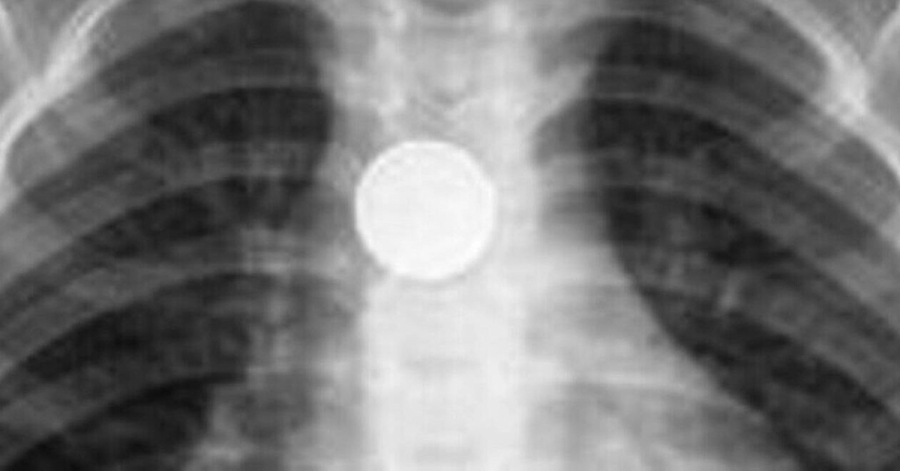

Αίσια έκβαση είχε η περιπέτεια για το τρίχρονο παιδί που κατάπιε ξυραφάκι και μεταφέρθηκε επειγόντως στο νοσοκομείο, όπου υπεβλήθη εσπευσμένα σε χειρουργική επέμβαση για να αφαιρεθεί το επικίνδυνο αντικείμενο.

Όπως εξηγεί παιδίατρος, συνηθέστερα αντικείμενα που καταπίνουν τα παιδιά, ηλικίας από 6 μηνών έως 4 ετών είναι νομίσματα, μπαταρίες, κουμπιά, παιχνίδια και μαγνήτες, τα οποία αν βρεθούν στον οισοφάγο ή στο στομάχι χρειάζονται άμεση εξαγωγή.